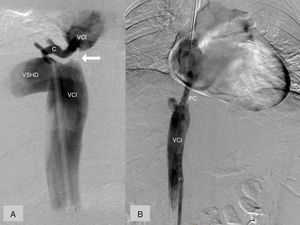

En una ecografía abdominal de control en 2015 se objetivó una imagen compatible con un CHC en el segmento 6 hepático de 2,7cm, confirmada mediante TC abdominal (fig. 1A). Ante una paciente con un CHC y signos de hipertensión portal (trombocitopenia y antecedente de ascitis) se planteó trasplante hepático5. Sin embargo, en la TC abdominal se objetivó que las VSH derecha e izquierda eran permeables, la vena media se encontraba ocluida, y había una estenosis de la parte superior de la VCI con formación de circulación colateral a nivel de la vena ácigos y venas lumbares (fig 1B); siendo pues una causa potencialmente tratable, se decidió realizar una cavografía con intención terapéutica. La cavografía informó de una obstrucción de la VCI por encima de la desembocadura de una vena suprahepática derecha dilatada, con una colateral próxima al punto de oclusión que conectaba con la VCI por encima de la estenosis (fig. 2A). Ante la imposibilidad de progresar la guía a través de la oclusión, se decidió conectar los segmentos supra e infra-estenosis mediante punción directa y colocación de una prótesis cubierta (Wallgraft® de 8mm de diámetro y 30mm de longitud). La cavografía de comprobación mostró un correcto paso de contraste a través de la prótesis con reducción significativa de la circulación colateral hacia el sistema ácigos (fig. 2B). En los controles posteriores al procedimiento, la paciente no presentaba ascitis y normalizó su cifra de plaquetas. Considerando, en este momento, que nos hallamos ante una paciente con una hepatopatía crónica, que en caso de haber desarrollado cirrosis sería clasificada como Child-Pugh A, sin signos de hipertensión portal, se consideró tributaria de una resección hepática.